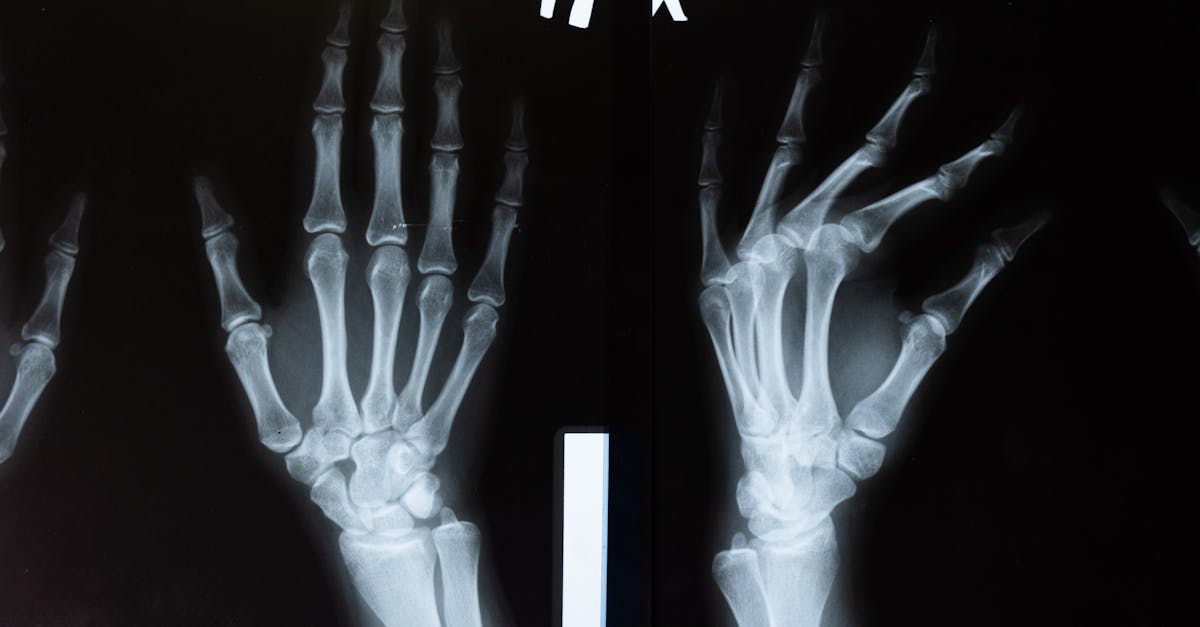

Le Tildren, ou acide tiludronique, s’intègre dans une classe spécifique de médicaments appelés bisphosphonates. Ces molécules ont pour fonction principale d’empêcher la résorption excessive de l’os en ciblant les ostéoclastes, cellules responsables de cette dégradation. Chez le cheval, plusieurs pathologies osseuses impliquent une altération ou une destruction accélérée du tissu osseux. Le Tildren cheval agit donc en stabilisant cette situation et en favorisant la cicatrisation.

Le traitement osseux cheval par Tildren est avant tout utilisé pour des affections telles que :

- L’arthrose équine : caractérisée par l’usure du cartilage et une inflammation des articulations, cette pathologie engendre douleur et boiterie.

- L’ostéochondrose : trouble du développement articulaire souvent rencontré chez les jeunes chevaux, causant des lésions au niveau du cartilage et de l’os sous-jacent.

- L’ostéite et l’ostéonécrose : infections osseuses ou nécrose cellulaire qui endommagent gravement le tissu osseux.

- Les fractures et lésions osseuses associées : notamment dans les cas où la densité osseuse est compromise.